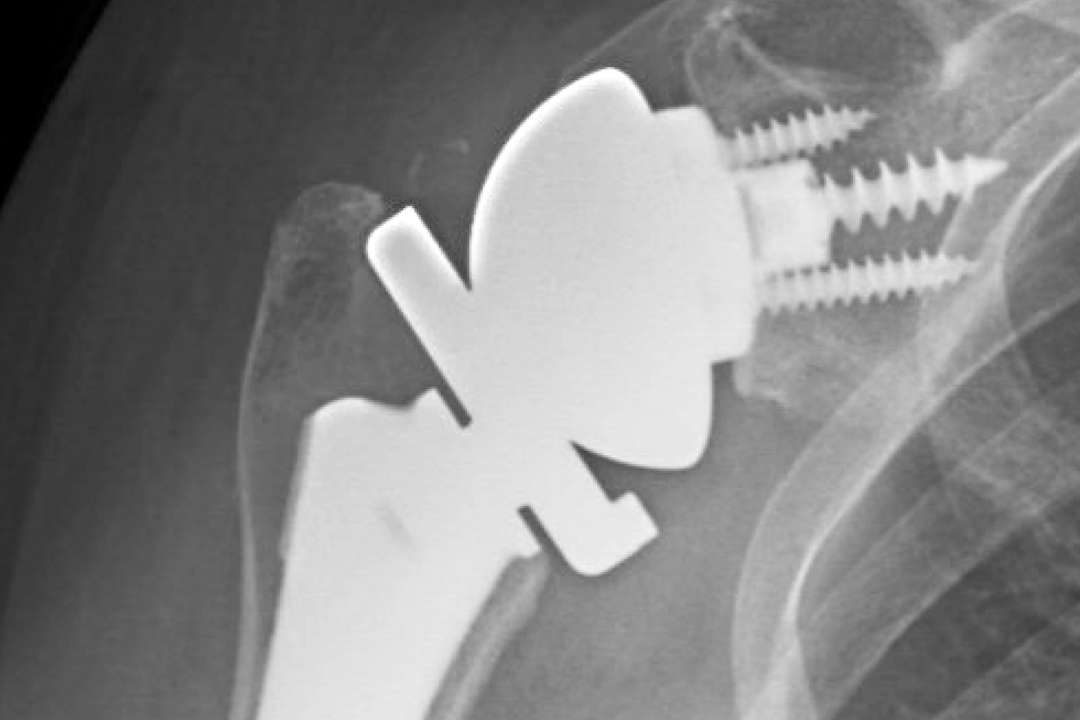

Is There Such A Thing As Shoulder Replacement Surgery . A plastic liner is then secured to the shoulder socket. Our orthopaedic surgeon edward mcfarland discusses the differences between a standard. Anatomic total shoulder replacement surgery replaces the damaged top of the humerus bone with a metal ball. Shoulder replacement surgery involves removing damaged parts of the shoulder bones and replacing them with prosthetic. A shoulder replacement is a procedure that tries to eliminate the source of pain and dysfunction by replacing damaged parts of the shoulder joint with artificial components. Total shoulder replacement, also known as total shoulder arthroplasty, is a procedure where portions of the bones in the shoulder joint are removed and replaced with artificial implants. Shoulder replacement is a surgical procedure in which all or part of the glenohumeral joint is replaced by a prosthetic implant. It helps restore the function and mobility of Shoulder replacement removes part or all of the shoulder joint to replace it with artificial implants, whereas rotator cuff surgery Rotator cuff surgery and shoulder replacement surgery are viable options for shoulder injuries and pain.